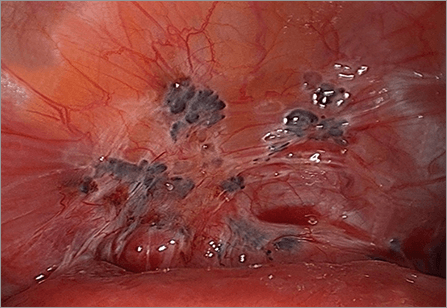

어느 정도 병변이 진행된 중증 자궁내막증은 질초음파나 혈중 CA125 농도를 통해 어느 정도 추정이 가능하나,

확진을 위해서는 복강경을 통환 관찰이 필요합니다.

당장 임신 계획이 없거나, 자궁내막종이 너무 크고 골반 내 장기의 변형이 심하다고 생각되거나 자궁내막증이 있는 상태에서

반복적으로 체외수정시술(시험관아기)에 실패한 경우에는 복강경을 통한 자궁내막종제거술 및 유착박리술을 시행합니다.